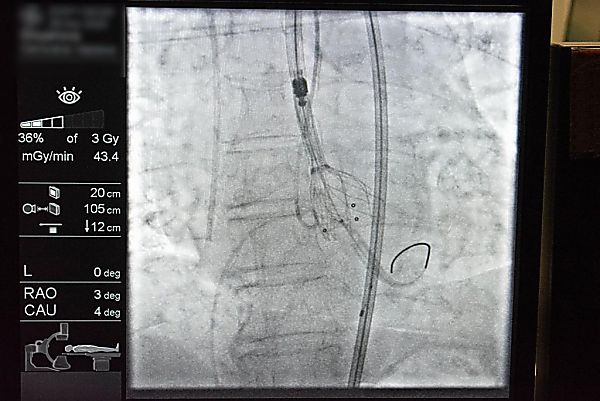

Екипът на Сърдечно-съдовия център на МЕДИКА участва активно в Симпозиума по интервенционална кардиология в Зайчар, Сърбия, от 27 до 29 ноември 2025 г. От четирите демонстрации на живо, три бяха проведени от русенските медици.

Проф. Добрин Василев демонстрира две ендоваскуларни процедури: транскатетърно имплантиране на аортна клапа (TAVI) и орбитална атеректомия. Д-р Октай Максудов извърши комплексна периферна реваскуларизация (PTCA).

Проф. Василев също така представи клиничен случай с комбинирано използване на SCA-DEB (балон с микронабраздяване и медикамент-отделящ балон), което впечатли аудиторията. Д-р Максудов представи случаи на лечение на периферни и коронарни заболявания чрез минималноинвазивни техники. Той подчерта значението на тези методи за подобряване на качеството на живот на пациентите и намаляване на риска от повторни интервенции. Неговото изследване привлече вниманието на международната аудитория, включително и на световноизвестния проф. Бернардо Кортезе от Кливланд, САЩ, който се включи онлайн в сесията, посветена на използването на DEB.